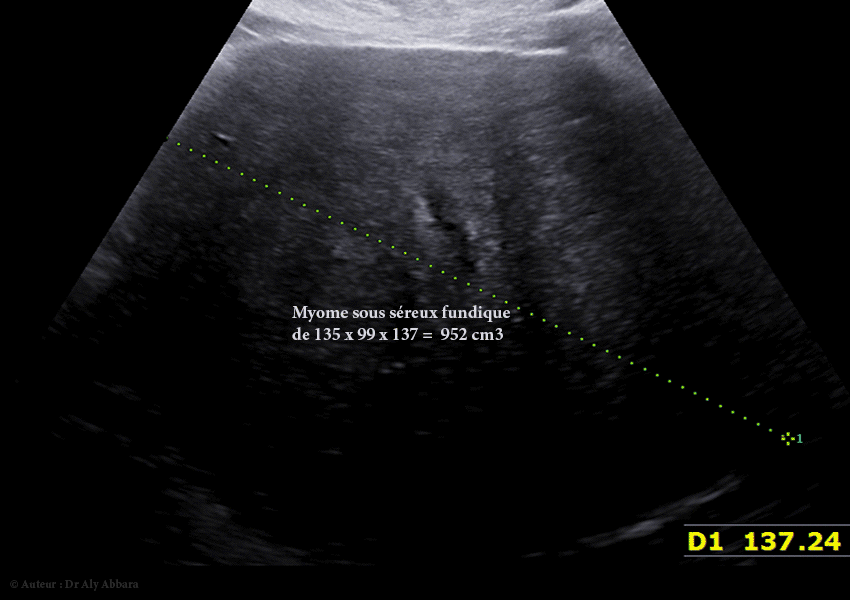

• Il s'agit d'un volumineux myome de 135 x 99 x 137 mm de diamètre, soit 952 cm3, asymptomatique, découvert fortuitement lors de la première échographie de datation (à 10 SA), chez une jeune femme, primipare de 31 ans.

• À 12 SA (952 cm3).